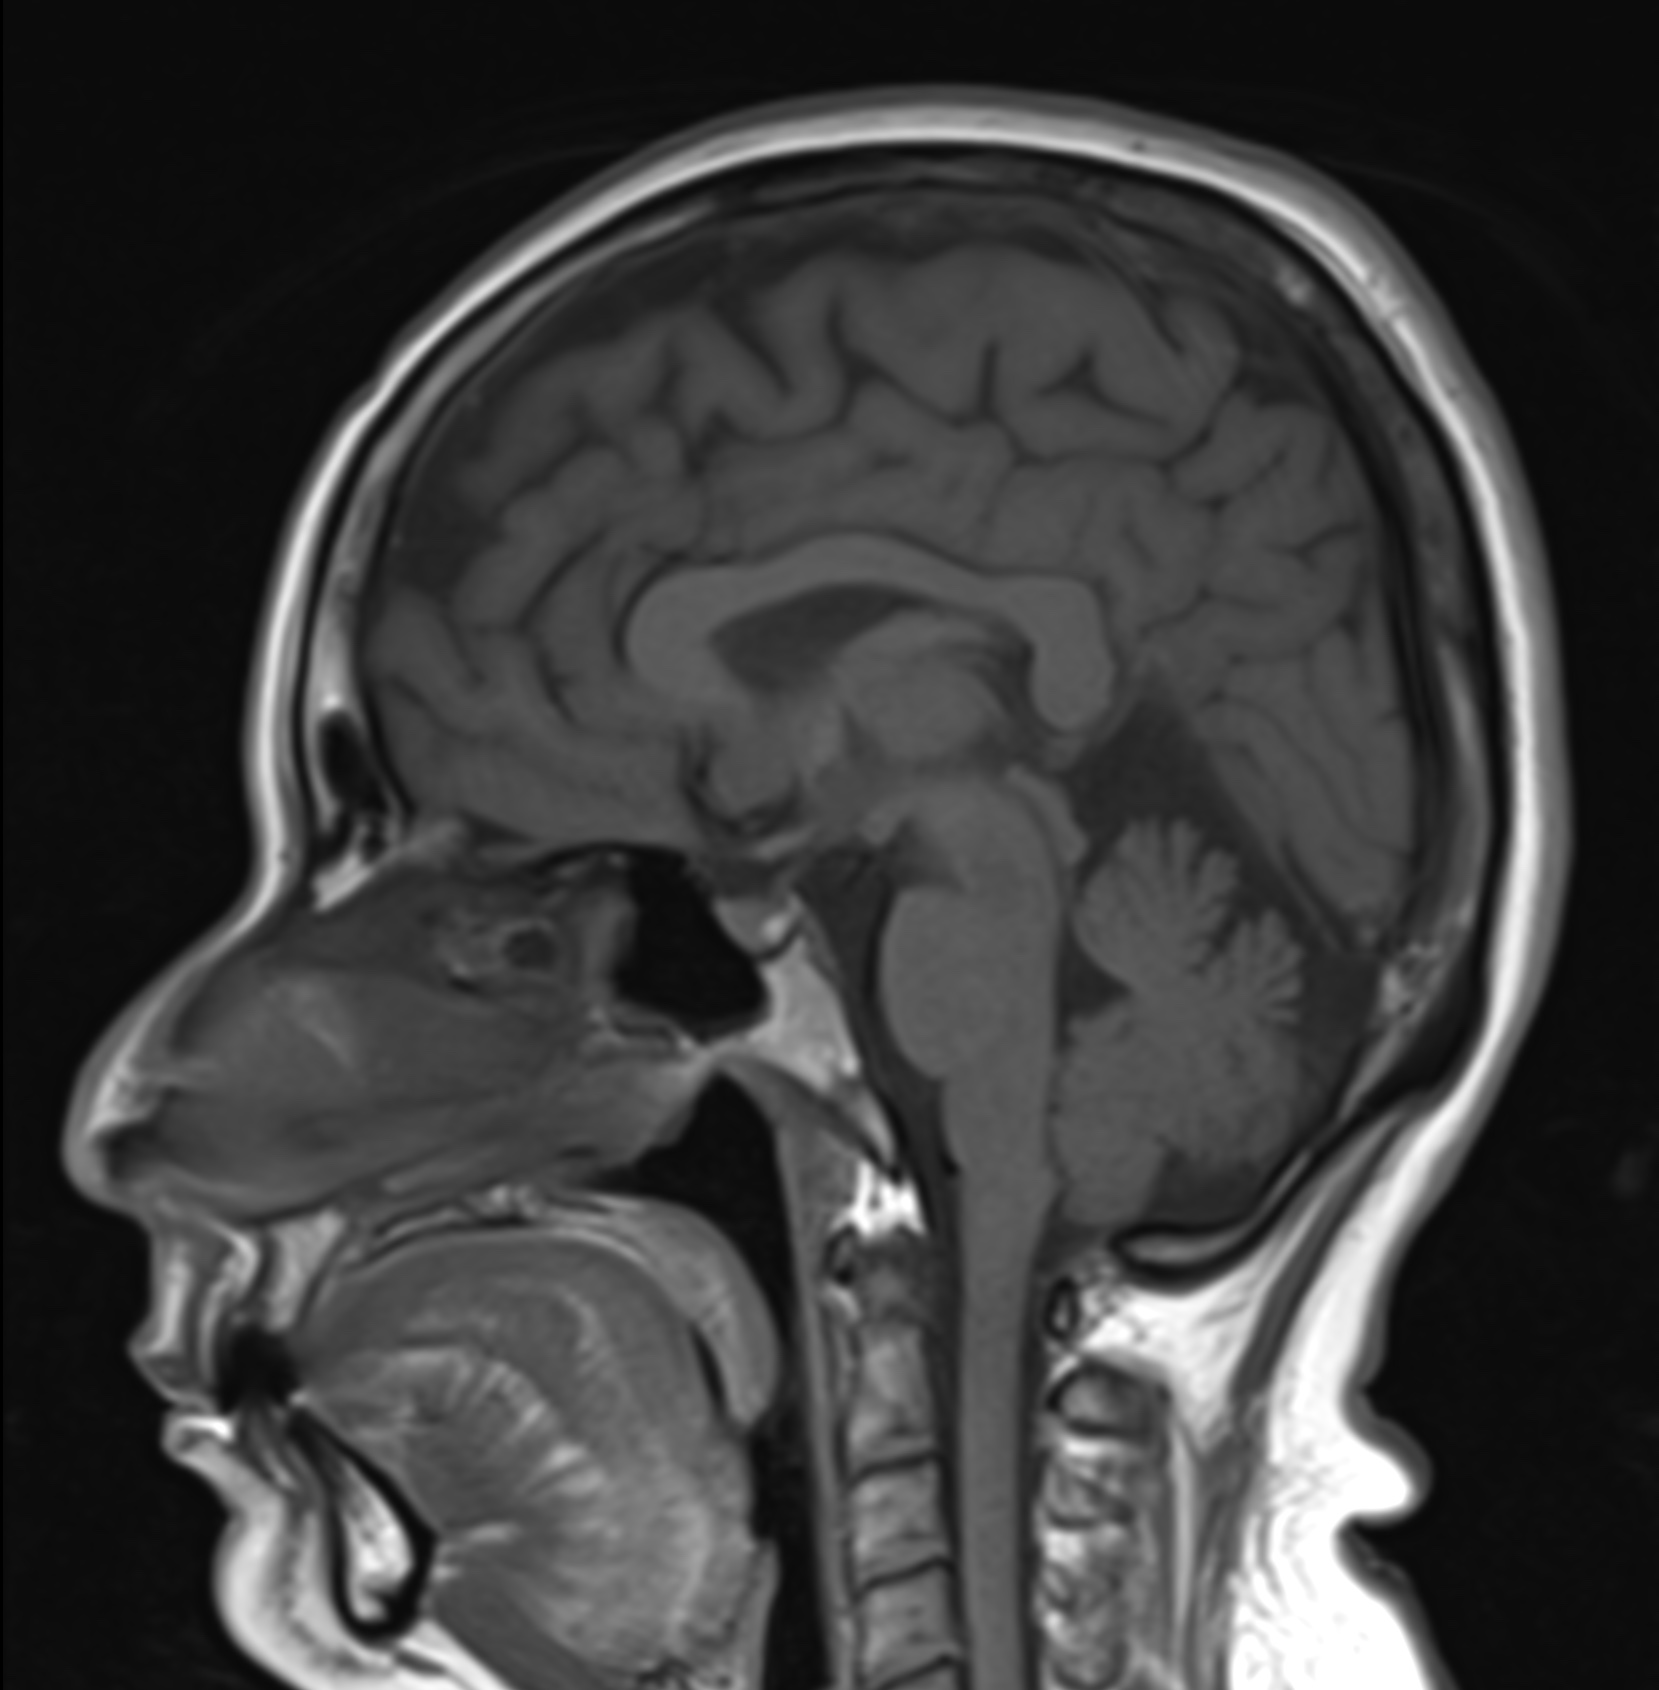

RM Cerebral

Nuestro examen resonancia magnética en el cerebro detecta, vigila enfermedades y trastornos como el sangrado de cerebro, anomalias congénitas, tumores(benignos, malignos) , la escleorosis múltiple, entre otros.